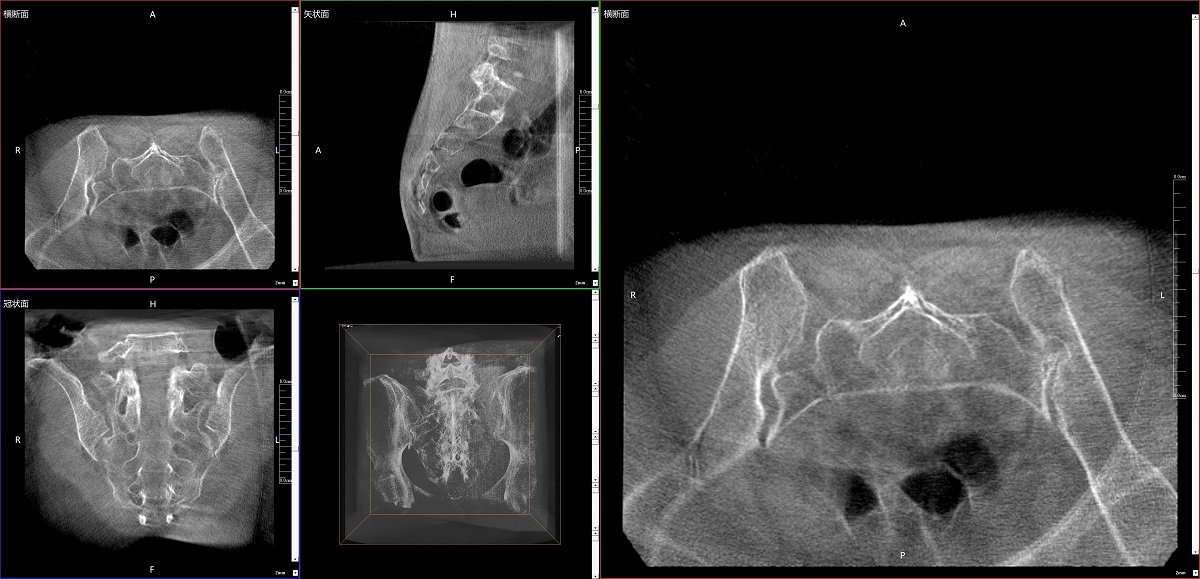

在骨科手術(shù)中,影像相當(dāng)于醫(yī)生的“眼睛”,要先“看得清",才能“算得準(zhǔn)” “打得穩(wěn)”。普愛醫(yī)療第三代平板三維C形臂協(xié)同醫(yī)院創(chuàng)傷導(dǎo)航機(jī)器人已開展多例“骨盆骨折微創(chuàng)手術(shù)”,成為上海市第七人民醫(yī)院手術(shù)技術(shù)創(chuàng)新的一大亮點。

普愛醫(yī)療第三代平板三維C形臂出色的二維透視和術(shù)中三維成像效果,為機(jī)器人提供了精確的術(shù)中影像依據(jù),協(xié)同提升手術(shù)整體的精準(zhǔn)度和效率,為患者帶來了更安全、更高效的醫(yī)療服務(wù)體驗。